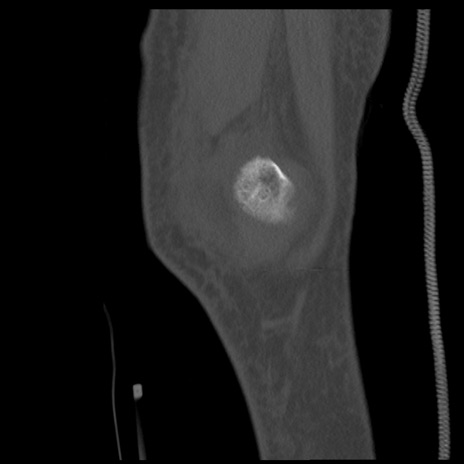

症例28 右膝関節CT(矢状断像)

右膝関節CT